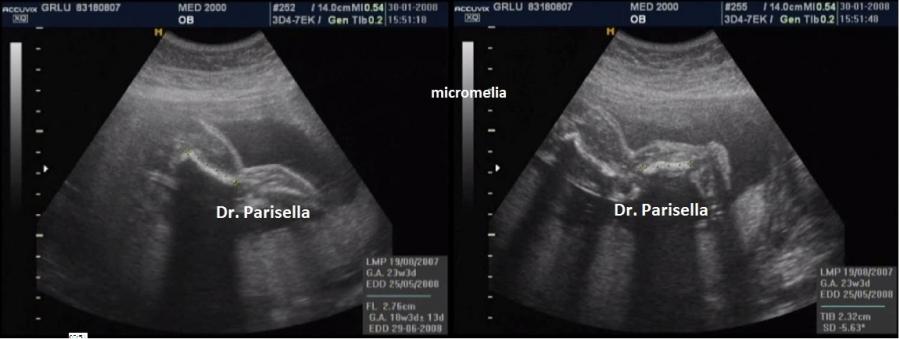

Così definita per le anomalie posturali e le contratture degli arti è una patologia generalizzata della cartilagine caratterizzata da distruzione della matrice cartilaginea, conseguente fibrosi e successiva ossificazione.

DIAGNOSI DIFFERENZIALE: si pone con l'artrogriposi dalla quale è facilmente riconoscibile per gli arti corti, il pollice da autostoppista ed i difetti del padiglione auricolare. Rispetto ad altre displasie scheletriche considerare che nelle displasia diastrofica le testa è sempre normale.

accurato studio ecografico